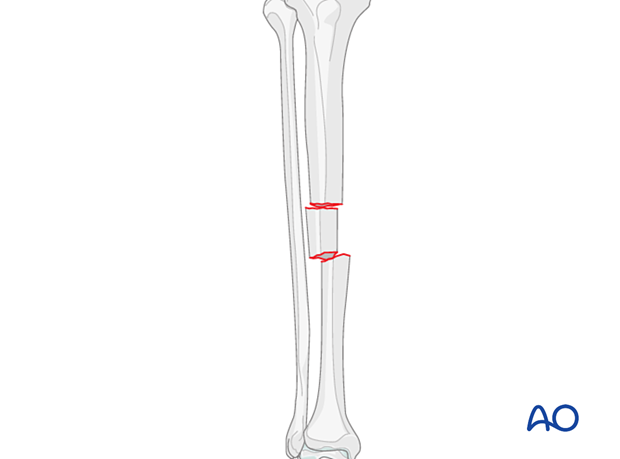

These fractures are classified as AO/OTA 42C2 fractures. These are complex fractures of the tibial diaphysis with an intermediate, intact segmental fragment. There is no contact between the main proximal and distal fragments.